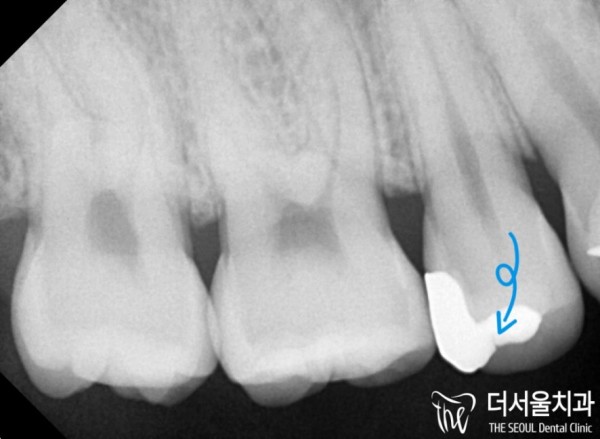

치근단 사진을 통해 해당 부분을 자세히 확인해보자

인레이에 파절이 생겼고, 이미 2차 우식이 생긴 상황이었습니다.

인레이 재 제작을 통해 치료할 수 있는 상황이었습니다.

Let's check the part in detail through the picture of the root of the tooth

There was a fracture in the inlay, and there was already a secondary caries.

It was a situation that could be treated through in-lay re-production.